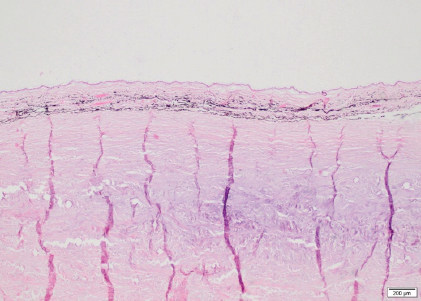

Fig . 1. Photographs of the fundus of the left eye of case 1 with a retinal detachment, giant retinal tear and partial disinsertion of the dorsal retina (A); normal fundus of the right eye of case 1 (B); subalbinotic fundus of the left eye of case 2 with a retinal detachment, giant retinal tear and partial disinsertion of the dorsal retina (C); normal sulabinotic fundus of the right eye of case 2 (D).

A giant retinal tear and partial disinsertion of the dorsal retina were observed OS. The retina was completely detached and radiated from the rim of the optic disk in transparent folds extending towards the posterior lens surface. The torn dorsal end of the retina had a typical scrolled and wrinkled appearance. These features were consistent with a rhegmatogenous retinal detachment (RRD).

The ophthalmic examination of the gelding was identical to that of the mare except for a lateral divergent strabismus with a slight rotation of the globe within the orbit OU regardless of head positioning. The ventronasal sclera were continuously exposed (Fig. 2A and B). The equator of the lens was visible OU after pupil dilation, and an incipient posterior cortical cataract was present OS (Fig. 2C and D). Intraocular pressure measured 27 mmHg OD and 26 mmHg OS.